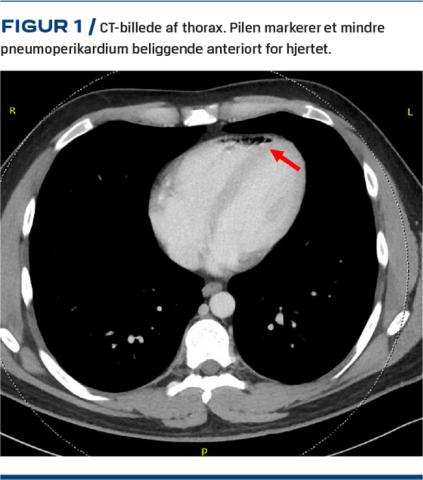

En 27-årig mand henvendte sig i en kirurgisk akutmodtagelse med diffuse mavesmerter, kvalme og opkastninger. Symptomerne var af timers varighed og kom turevis med dages mellemrum.De havde stået på i flere måneder. Det lindrede, når han tog varme badeeller røg cannabis, som han havde haft et dagligt forbrug af i over ti år. Han røg også cigaretter, men benægtede nogensinde at have røget kokain, heroin eller at have taget lattergas. I modtagelsen blev der lavet en CT af abdomen, hvor man fandt normale abdominale forhold, men i den medskannede del af thorax, som nåede til niveau med Th5, sås et mindre, isoleret pneumoperikardium beliggende anteriort over venstre ventrikel (Figur 1). Skanningen viste ingen tegn til pneumomediastinum, pneumothorax eller anden patologi, og patienten havde ingen torakale eller kardiopulmonale gener. Der blev ikke foretaget toksikologisk screening af blod eller urin. Patientens mavesmerter svandt spontant under opholdet i akutmodtagelsen, og han overgik til kardiologisk regi til vurdering. Den indledende vurdering med ekg og transtorakal ekkokardiografi viste normale forhold, og hanvar helt upåvirket.

Pneumoperikardium associeret med cannabisbrug forekommer sjældent, men er formentlig underdiagnosticeret, da det typisk vil være et tilfældigt fund i forbindelse med billeddiagnostik i andet øjemed [2]. Den tilgrundliggende mekanisme menes at være barotraume mod luftvejene forårsaget af kraftig hoste og evt. opkastninger ved rygning af cannabis samt ved Valsalvas manøvre, som udføres med det formål at få større virkning af stoffet ved inhalation [2,4,5]. Det høje intratorakale tryk forårsager skade på alveolerne, så luft kan trænge ind i det interstitielle rum og derfra dissekere langs karskederne af de store kar til hjertet og ind til perikardiet [5]. Tilstanden kan påvises ved CT eller MR-skanning af thorax eller ved konventionel røntgenoptagelse af thorax f.eks. ved continuous diaphragm sign, hvorved diafragmas øvre grænse kan følges under hjerteskyggen. Ved transtorakal ekkokardiografi kan der evt. ses air gap sign eller swirling bubbles sign, som er artefakter, der fremkommer ved ultralydbølgernes refleksion mod luften. Ved auskultation kan der evt. høres bruit de moulin, som er en rytmisk plaskende mislyd, der minder om vandmøllehjuls plask mod vandet, eller Hammans tegn, som er en knitrende mislyd synkron med hjertets slag.